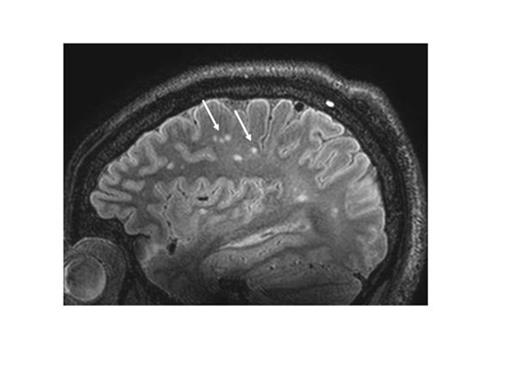

With the exception of two patients, all displayed round and circumscript infarcts in the deep white matter of the frontal or parietal lobe (Table). Most lesions (82%) were <5 mm. In one patient (A) we identified 164 white matter infarcts (Figure 1). Strikingly, one patient (patient B) had several cortical micro-infarcts (Figure 2) although she had no neurological symptoms. These were associated with an occluded A1 and A2 segment of the anterior cerebral artery. In addition, this patient had unique pattern of white matter lesions, consisting of irregular shaped white matter infarcts, some located periventricular, and others close to the cortical infarcts. In two other patients (patients C and D) we identified an isolated cortical micro-infarct despite the absence of large vessel vasculopathy. In patient C, we found numerous hypo-intense areas symmetrically distributed in the deep white matter of the frontal and parietal lobe (Figure 3). These areas were associated with prominent transmedullary veins.

Typical pattern of white matter infarcts (arrows) in patient A, 7T MP-FLAIR image.